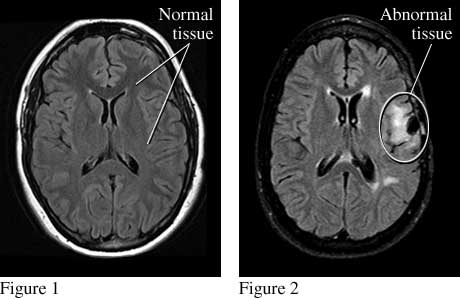

Seizure MRI